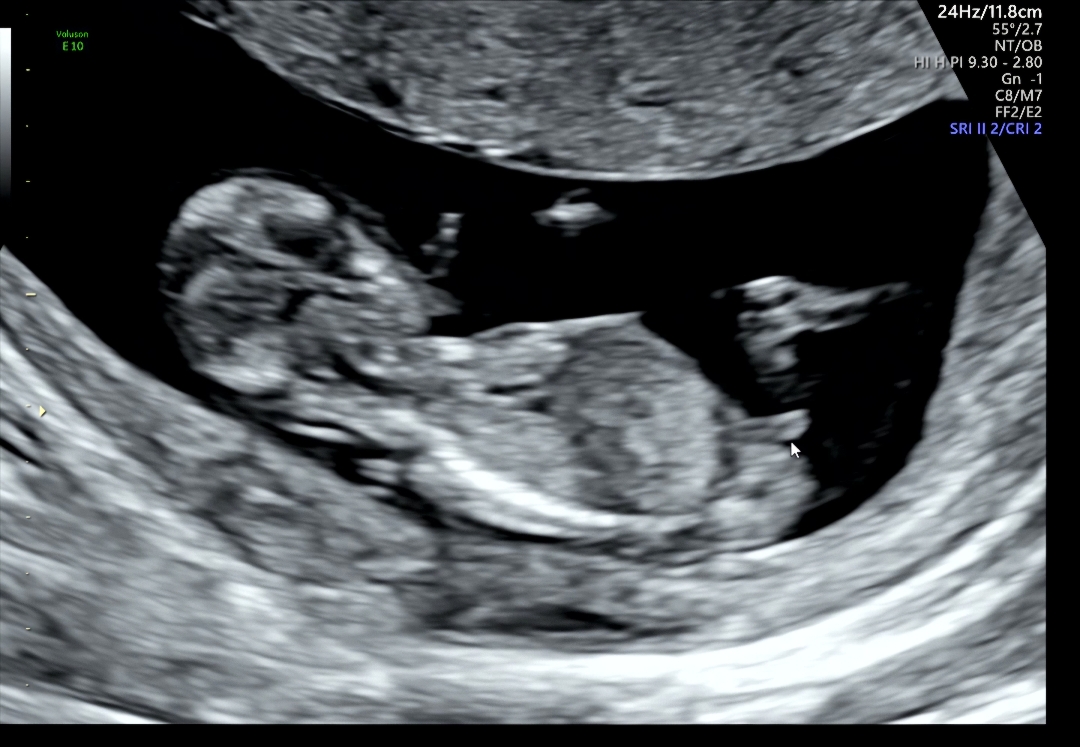

12주 3일 각도법 봐주세요

딸일까요, 아들일까요? 각도법 고수님들 한번 봐주세요 🙏